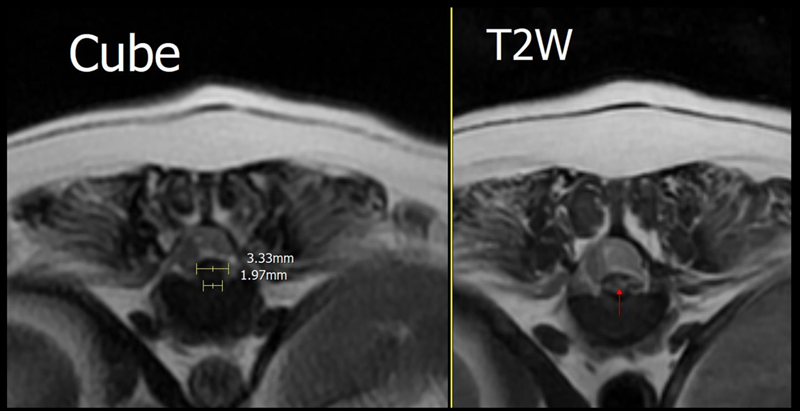

흉단면상 T12/13 디스크 돌출은 좌측에 편향되어 척수 신경 압박하고 있으며 탈출된 디스크 물질은 Cube & T2W sequence 모두 돌출된 디스크 가장자리가 바닥보다 넓은 양상으로 관찰되어 disc extrusion (type I) 의심됨 (압박률 28%) ▼